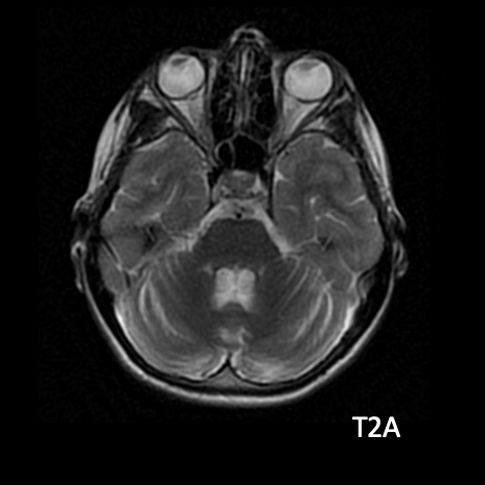

- B) Aksiyel T1A görüntülerde her iki lentiform ve kaudat nukleuslarda, talamuslarda simetrik hiperintensite (oklar) izleniyor. Bu düzeyde tariflenen sinyallerin SWI ve faz görüntülerde kalsifikasyon ile uyumlu olduğu görülmektedir (oklar). T2A görüntüde yaş ile uyumsuz serebellar atrofi ile uyumlu foliada derinleşme ve 4. ventrikül genişliğinde artış izlenmektedir (oklar).

- BT’de birden fazla lokalizasyonda multipl enfarkt benzeri odaklar ve özellikle ileri yaş hastalarda belirginleşen bazal gangliyon kalsifikasyonları izlenebilir. Lezyonlar çoğunlukla pariyeto-oksipital ve pariyeto-temporal bölgelerde yoğunlaşır ve serebral atrofi eşlik edebilir.

- MRG’de akut fazda T2/FLAIR hiperintensiteyle birlikte giral şişme ile karakterize enfarkt-benzeri lezyonlar ve subkortikal beyaz cevher tutulumu görülür. DWI’da artmış sinyal dikkat çekmekle birlikte ADC değerlerinin normal ya da hafif artmış olması, baskın sürecin vazojenik ödem olduğunu gösterir.